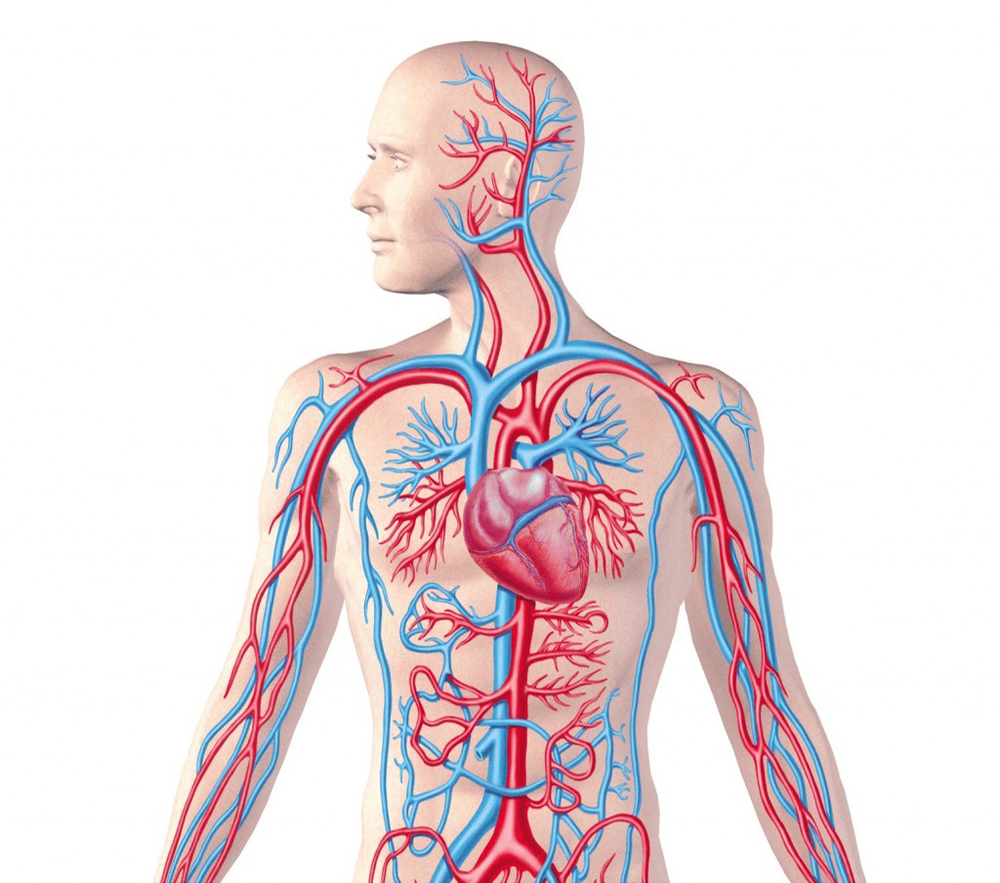

Mỗi tế bào trong cơ thể người đều được cung cấp dinh dưỡng từ hệ thống mạch máu. Đồng thời, trong mỗi tế bào quá trình tổng hợp các hợp chất hữu cơ phức tạp từ những chất đơn giản luôn luôn diễn ra.